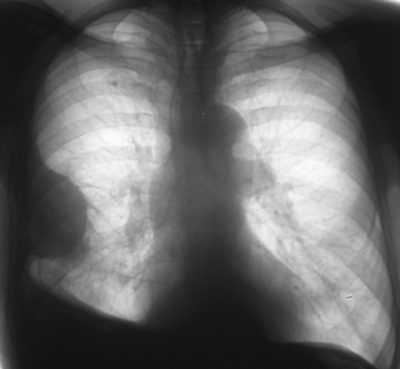

Экссудат может осумковываться частично или полностью. При первом варианте плевральные спайки образуют 1-2 стенки «сумки», вследствие чего возможно перемещение жидкости при смене положения тела. При полномосумковании экссудат ограничивается сращениями листьев плевры со всех сторон. На рентгене он будет выглядеть одинаково, независимо от положения пациента. Кроме того, различают одиночные и множественные зоны осумкования. Недуг бывает односторонним или двухсторонним.

На снимке, сделанном в трех проекциях (прямая, боковая и косая) обнаруживаются характерные участки затемнения. В сложных и сомнительных случаях необходимо наложить искусственный пневмоторакс и пневмоперитонеум или провести компьютерную томографию легких.